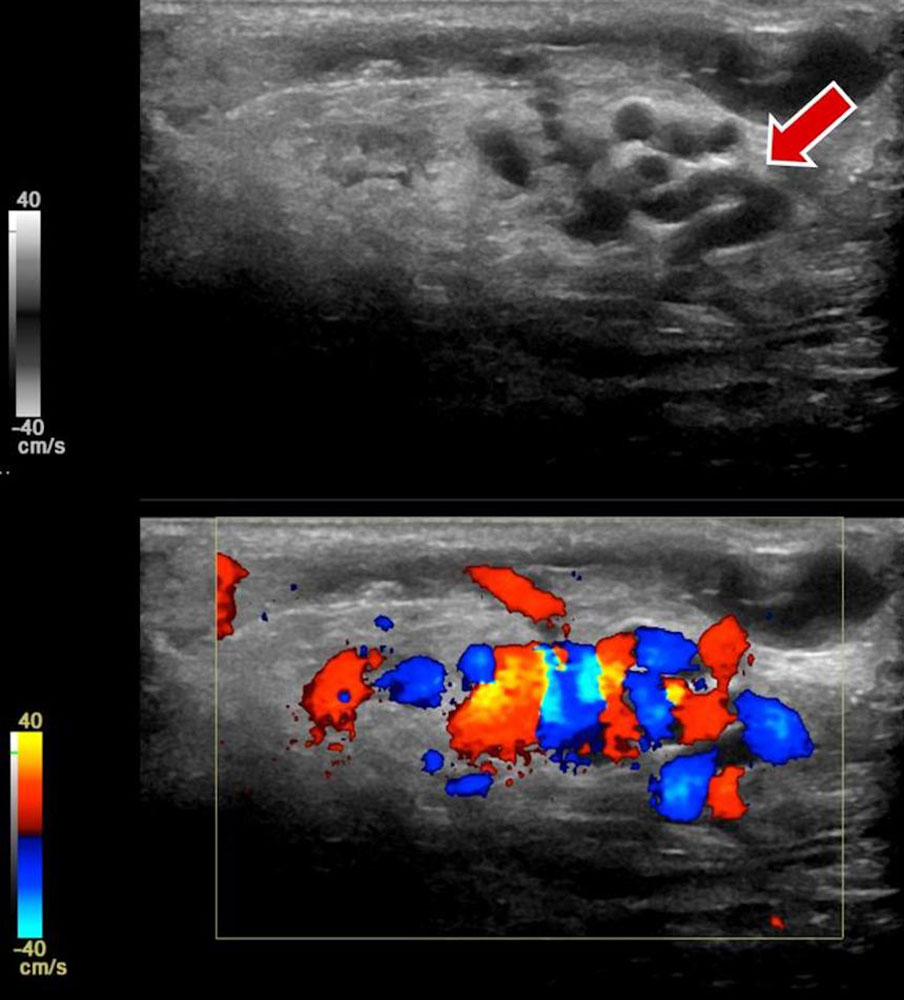

• Arteriovenous malformation: The main characteristic of peripheral arteriovenous malformation (AVM) is hyperperfusion, which can be easily detected on color-coded duplex sonography. A Doppler examination of the afferent arteries often does not show the usual triphasic resistance pattern in the affected limb, but an increased diastolic forward flow. The venous outflow also shows a significant increase in flow on the affected side. The typical respiratory variability of the venous blood flow is lacking; the high flow rate results in a continuous forward flow in draining veins. Inflowing and outflowing vessels often have a significantly larger diameter compared to the unaffected side. A supplementary examination of cardiac function by echocardiography is recommended for patients with large fast-flow vascular malformations (see special chapter on Cardiac complications).